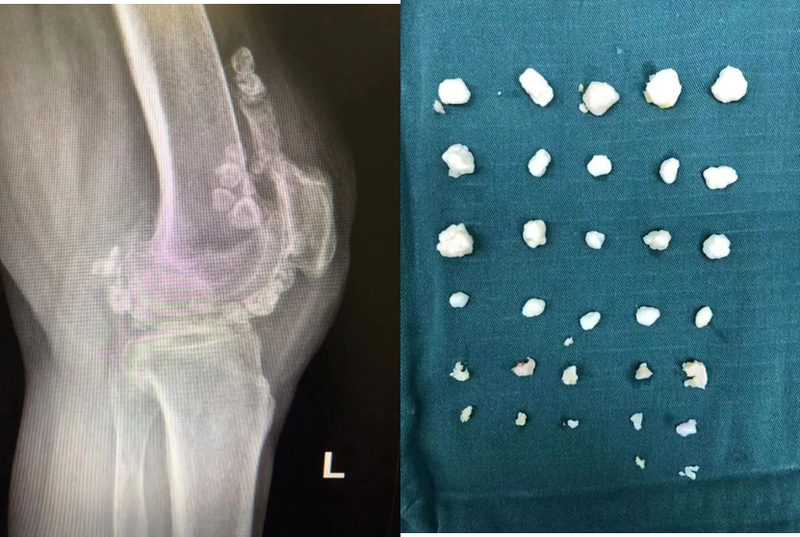

滑膜軟骨瘤病(SC)又稱滑膜骨軟骨瘤病、滑膜軟骨化生等,是一種多發(fā)生在關(guān)節(jié)腔內(nèi),以關(guān)節(jié)滑膜、肌腱腱鞘滑膜及滑囊內(nèi)形成多個(gè)軟骨結(jié)節(jié)為特點(diǎn)的罕見良性病變。惡變?yōu)榛ぼ浌侨饬龅母怕蕿?%~5%?!静∫颉勘静〔∫蛏胁磺宄?。1、本病系起源于關(guān)節(jié)滑膜,是滑膜下結(jié)締組織化生的結(jié)果。2、是滑膜長期受慢性創(chuàng)傷或炎癥刺激,反應(yīng)性增生所致。3、是間充質(zhì)細(xì)胞在分化成滑膜或軟骨過程中,一部分細(xì)胞受阻,日后發(fā)育成本病有關(guān)?!静±怼?.大體所見肉眼見滑膜有不同程度增厚、充血,在薄的被覆層下有很多大小不等的軟骨結(jié)節(jié)。這些軟骨的質(zhì)地較堅(jiān)實(shí),屬透明軟骨。切面呈白色有沙捻感,成熟的軟骨結(jié)節(jié)可自滑膜脫落后進(jìn)入關(guān)節(jié)腔,形成游離體,數(shù)量可多達(dá)上百個(gè),體積大約為直徑1~2cm。根據(jù)病理將本病分為三期:①活動性滑膜病變;②過渡性滑膜病變合并滑膜軟骨瘤及游離體;③滑膜病變靜止形成多數(shù)游離體。2.鏡下所見鏡下見滑膜結(jié)締組織有軟骨化生,有時(shí)可見成片的成纖維細(xì)胞腫大向軟骨細(xì)胞過渡,開始形成軟骨。生長的軟骨結(jié)節(jié)周圍有纖維囊包裹。軟骨結(jié)節(jié)均由成熟的透明軟骨為主要成分。